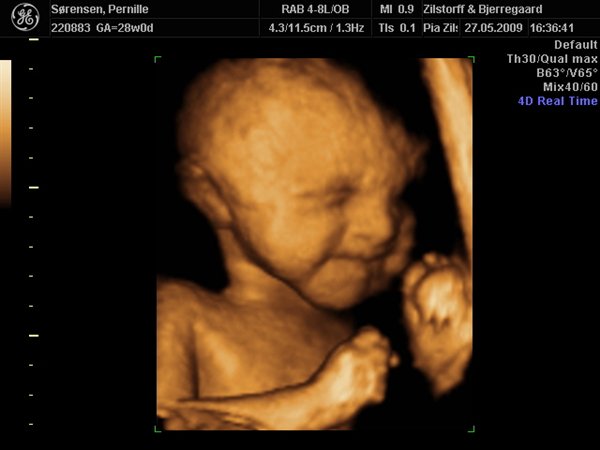

Det jeg har fået af vide er at jeg er i risiko for at føde for tidligt og derfor er jeg under observation og går til kontrolskanning og lægesamtaler hver 14. dag.

Der er vidst også risiko for at lillepigen får svært ved at sætte sig fast med hovedet og så kan jeg ende i kejsersnit.

De troede i første omgang at det skyldte sukkersyge, men det har jeg da (heldigvis) fået udelukket. Sidsta gang fik jeg taget en masse blodprøver for at tjekke for infektioner - hvis det heller ikke er årsagen, ja så ved de det vidst ikke!